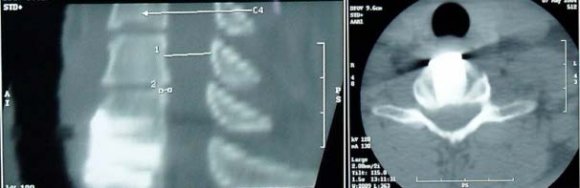

In both types of implants (glassceramics/bioactive titanium) developed by us we indicated patients for the operation according to the instability of the injured lower spine defined in the preoperational stage according to the imaging methods (X-ray, MRI, CT) and using the classification according to Aebi and Nazarian and according to the neurological findings using the Frankel scale. We carried out the surgery by the Caspar technique (Caspar 1989, Klézl 1999). Under general anesthesia from the prevertebral incision and after exposing anterior surface of the veretbral bodies we removed the structures compressing the spinal canal (intervertebral disk, posterior ligament residues, fragments of the edges of the vertebral bodies, haematoma, etc.) using an operating microscope. Then we prepared a bed for inserting the implant into the interbody space. We removed the endplates from the vertebral bodies and exposed cancellous bone. In traction and using the Caspar´s instrumentarium we inserted the implant into the interbody space under the control of X-ray, see Figure 7.

Figure 7 : Inserting the bio-titanium implant into the interbody space C5/6 using the X-ray control After releasing traction and checking the position on X-ray we fixed the impaired segment by a plate secured with monocortical or bicortical screws into the neighboring vertebral bodies. Surgical procedure is similar for both the glass-ceramics implant and the biotitanium implant. We used the same surgical procedure for other types of implants as well (polyactide/PEEK). We carried out verticalization in operated patients in case of all implants on the first post-operative day in a collar for a period of 6 weeks until the expected bone fusion occurrence.

At Neurosurgery Department of the University Hospital in Ostrava we operated 10 patients with unstable injury to the lower cervical spine using glassceramics implants between 1997 and 1999, see Figures 9 and 10 The implant for use in ACIF made of glassceramics fulfilled our expectations. It removed complications associated with bone graft harvest and due to its shape and bioactive properties it enabled a chemical bond with surrounding osseous tissue to create bone fusion without a need for filling with other material (Bienik 1991,Madawi 1996, Filip 2000). Its disadvantages included fragility in contact with metal and threshold bending strength. These disadvantages were eliminated by a new implant made of bio-titanium that we introduced into clinical practice for identical indications in 2004. In years 2007-2011 at the Neurosurgery Department of KNTB Zlín we operated 34 patients with unstable lower cervical spine injury. In 12 patients we used a bio-titanium implant in ACIF (Figures 11 and 12). In 22 patients we used an implant made of different materials (Figure 13). In our own set of patients we evaluated the neurological finding according to the Frankel scale with a finding from the imaging methods (X-ray, CT, MRI) preoperative and 2, 6 and 12 months after the surgery.